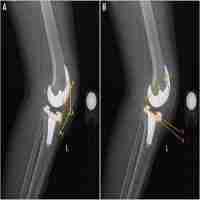

| Abstract | Knowledge of anterior–posterior (A-P) tibial contact locations provides an objective assessment of the relative motion of the tibia on the femur following total knee arthroplasty (TKA), which can be used to compare the effects of different components, surgical techniques, and alignment goals on knee function in vivo. Both the lowest point method and the penetration method have been used to calculate A-P tibial contact locations using three-dimensional (3D) model to two-dimensional (2D) image registration. The primary objective of this study was to quantify errors in calculating the A-P tibial contact location using the lowest point and penetration methods because the errors in calculating the A-P tibial contact locations using these two methods are unknown. The A-P tibial contact locations were calculated with the two methods and simultaneously measured with a tibial force sensor in ten fresh-frozen cadaveric knee specimens with a TKA. Single-plane radiographs of the knee specimens were acquired at 0 deg, 30 deg, 60 deg, and 90 deg of flexion in neutrally, internally, and externally rotated orientations. While the radiographs were exposed, reference A-P tibial contact locations were simultaneously collected using the tibial force sensor to be compared to the calculated A-P tibial contact locations. The overall root-mean-squared-errors (RMSEs) in the A-P tibial contact location calculated with the lowest point method, the penetration method with penetration, and penetration method without penetration were 5.5 mm, 3.6 mm, and 8.9 mm, respectively. The overall RMSE was lowest for the penetration method with penetration, making it the superior method for calculating A-P tibial contact locations. |